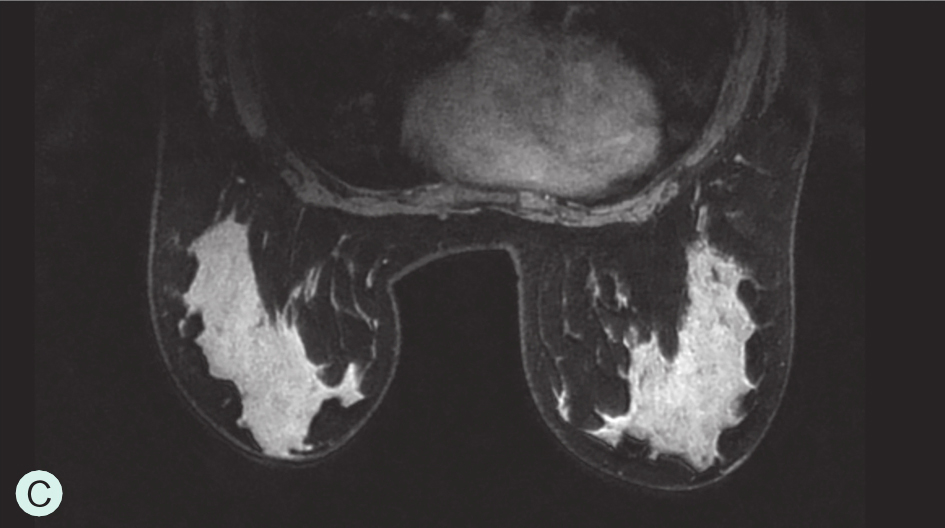

图1-3-3 乳腺MRI不同乳腺密度

A.脂肪型;B.散在致密型;C.不均匀致密型;D.极度致密型

D级:极度致密型(降低乳腺钼靶摄影的敏感性)(图1-3-1D、图1-3-2D、图1-3-3D)。